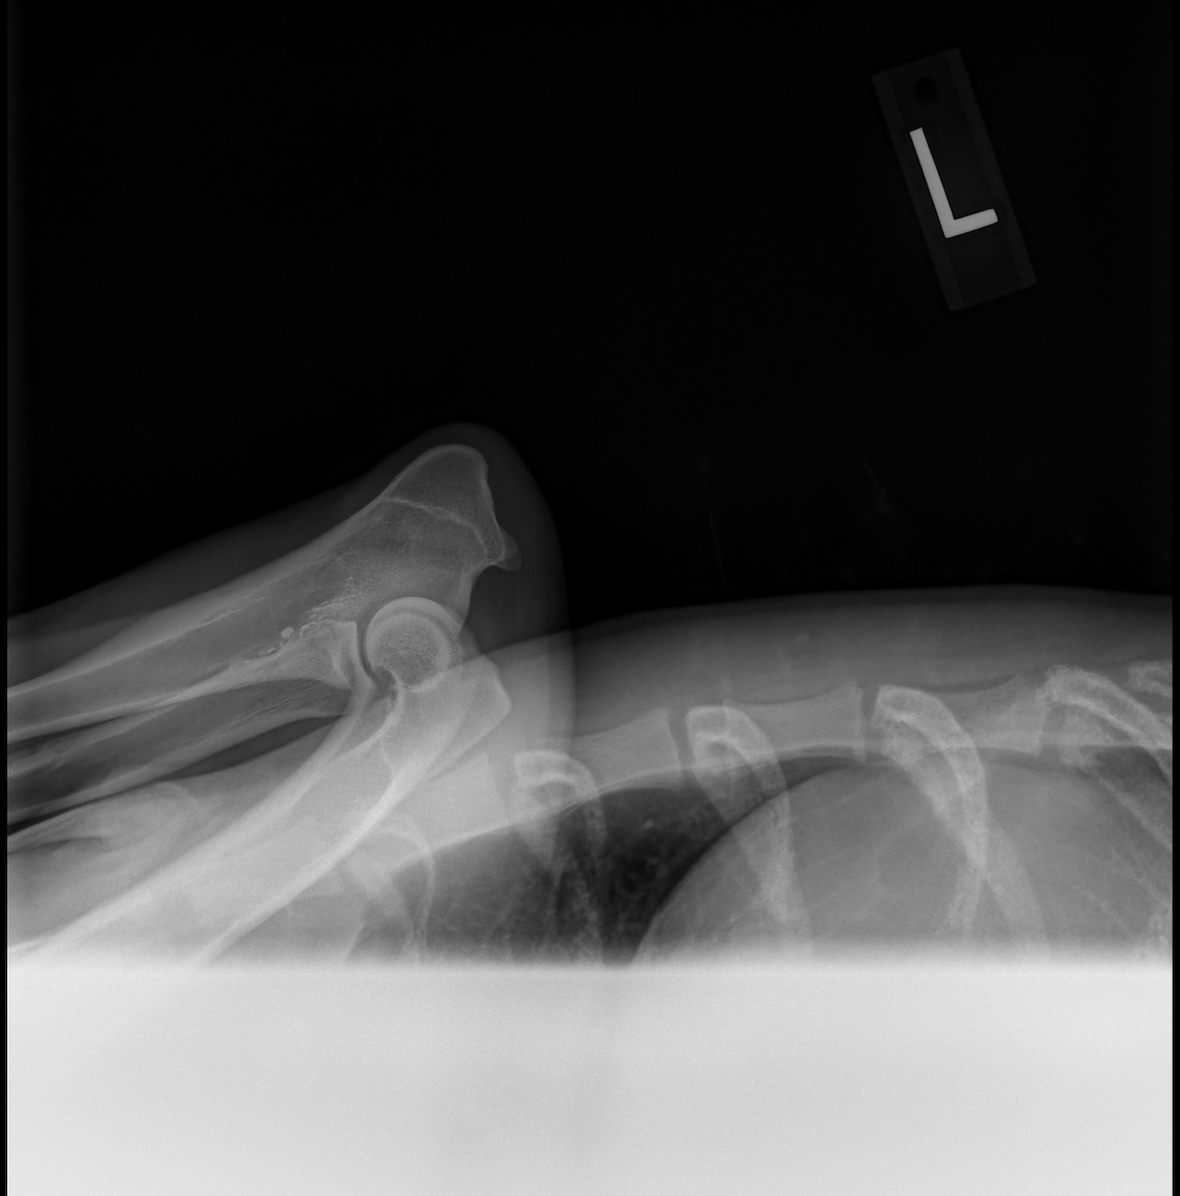

---- OFA Hip & Elbow Imaging ----